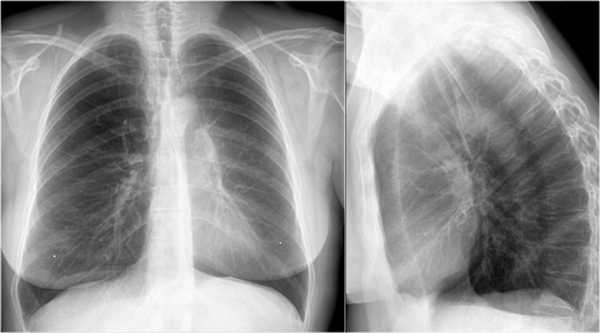

Ателектаз средней доли правого легкого.

- Симптом силуэта — нечеткие границы правых отделов сердца.

- Трехгранные изменения высокой плотности, визуализирующиеся на боковой рентгенограмме, являются результатом ателектаза средней доли правого легкого.

При ателектазе средней доли правого легкого подъем диафрагмы навсегда значительно выражен.